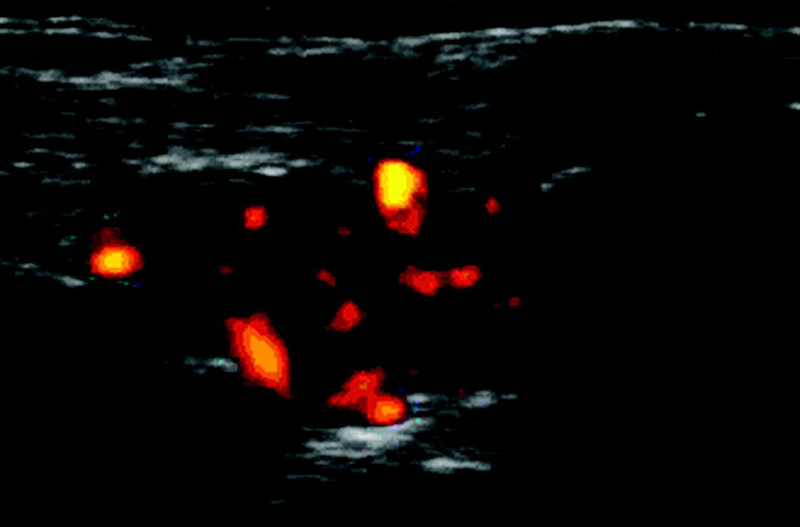

Siêu âm sử dụng sóng âm tần số cao để tạo ra hình ảnh các cơ quan và mô trong cơ thể. Bác sĩ sẽ bôi một lớp gel mỏng lên da, sau đó đặt đầu dò lên vùng cơ thể (tùy bộ phận bị ảnh hưởng). Đầu dò chuyển đổi dòng điện thành sóng âm tần số cao và truyền vào cơ thể. Sóng âm dội lại từ cấu trúc bên trong và trở lại đầu dò. Đầu dò chuyển sóng thành tín hiệu điện. Máy tính sẽ chuyển tín hiệu điện thành hình ảnh, video.

Sóng siêu âm có thể dùng để chẩn đoán các vấn đề về xương khớp: